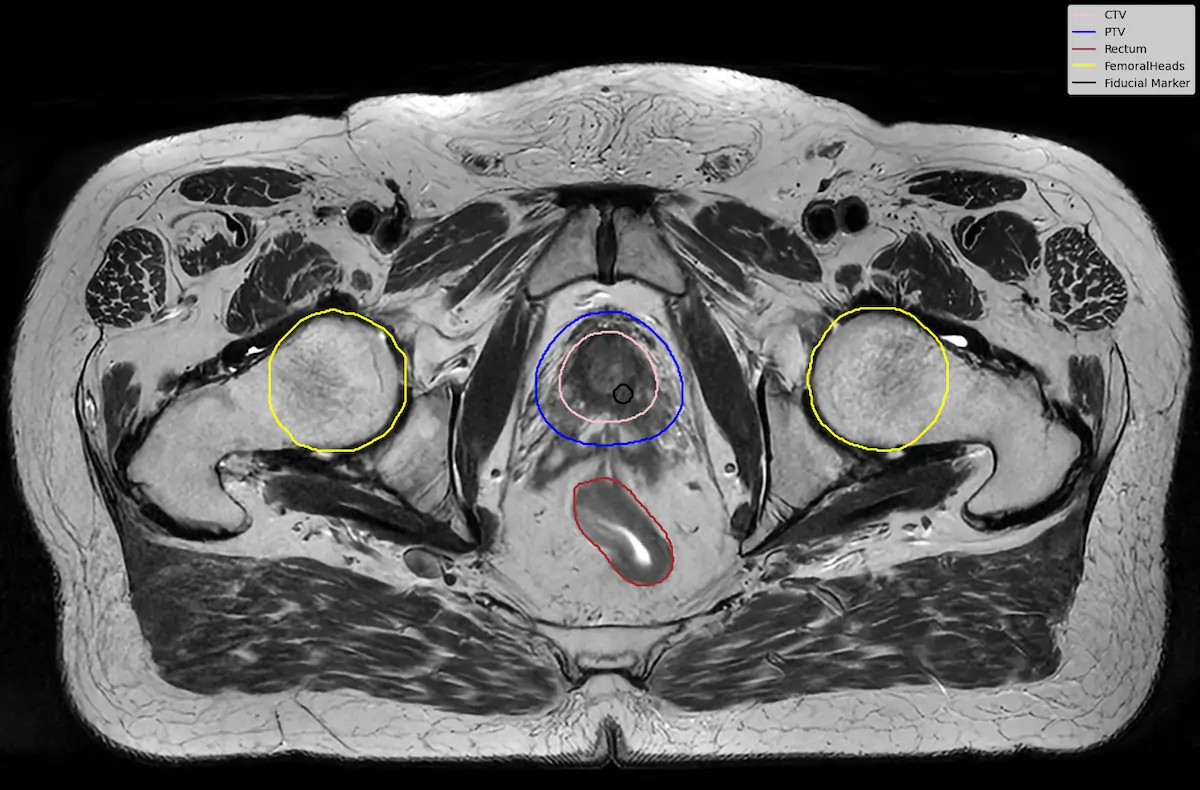

To test this idea, we performed a small downstream experiment using the LUND-PROBE dataset from Lund University [7]. The dataset contains multiparametric prostate MRI scans collected as part of the PROBE study, aimed at developing AI methods for improved prostate cancer detection and diagnosis. The data is de-identified and curated for research purposes, making it a valuable benchmark for medical imaging tasks.